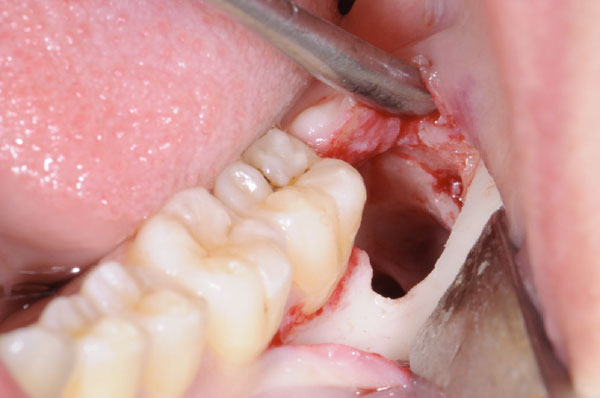

L'intervento segue precisi protocolli chirurgici. Dopo l'esecuzione di un'anestesia loco-regionale, si procede all'allestimento di un lembo di accesso mucoperiosteo a spessore totale, la cui scelta è determinata principalmente dalla profondità dell'inclusione e dalla posizione del terzo molare. In tutti i casi, il lembo deve creare un sufficiente accesso chirurgico (visivo e strumentale), evitare le strutture anatomiche circostanti (nervo linguale, arteria facciale), consentire un corretto riposizionamento del lembo e un'agevole sutura.

L'utilizzo dello strumentario piezoelettrico rappresenta una valida alternativa nei casi di ostectomia profonda e per l'avulsione di residui radicolari in stretto rapporto con strutture anatomiche nobili.